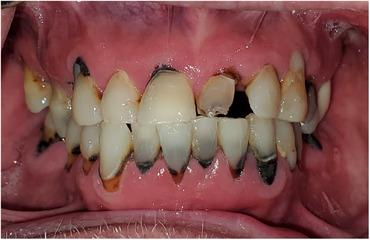

A Targeted Approach to Dental Treatment for Patients Prior To and After Head and Neck Radiation.

This is a narrative review of contemporary radiotherapy for head and neck cancers, the role of pre-radiation dental clearance, and rationale for a targeted approach to pre-radiation treatment. Emphasis is placed on avoiding delay in the start of radiation. The goals of this article are to facilitate communication between the dentist and radiation oncologist, succinctly summarize current recommendations, and give suggestions on what qualifies as high priority dental care in the pre-radiation setting.